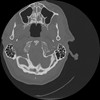

7 HUESO,,Vol,0.5,HUESO,,